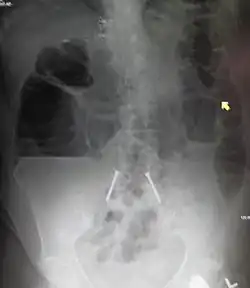

Upright abdominal X-ray demonstrating a small bowel obstruction. Note multiple air fluid levels.

Radiological signs of bowel obstruction include bowel distension (small bowel loops dilated >3 cm) and the presence of multiple (more than 2) air-fluid levels on supine and erect abdominal radiographs.[16] Ultrasounds may be as useful as CT scanning to make the diagnosis.[17]